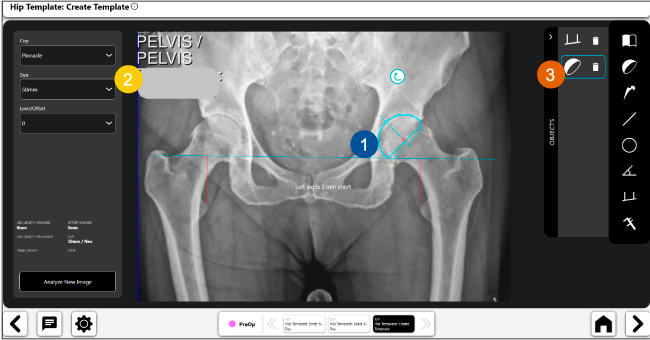

Planeación preoperatoria mediante la creación de plantillas digitales para reemplazo de cadera y análisis intraoperatorio

• Disponibilidad de plantillas digitales de cadera.

• Expediente histórico y personalizado, optimiza la planeación con el calendario de casos realizados en Velys TM y utiliza los íconos interactivos para una rápida revisión.

• Espacio colaborativo: puede compartir los casos entre cirujanos y sus equipos mediante la funcionalidad de intercambio de información.